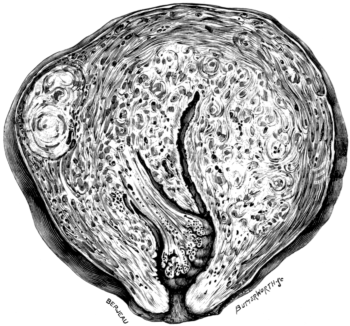

| 1. | Secondary Cancer of the Ovary | 15 |

| 2. | Secondary Cancer of the Ovary in Section | 15 |